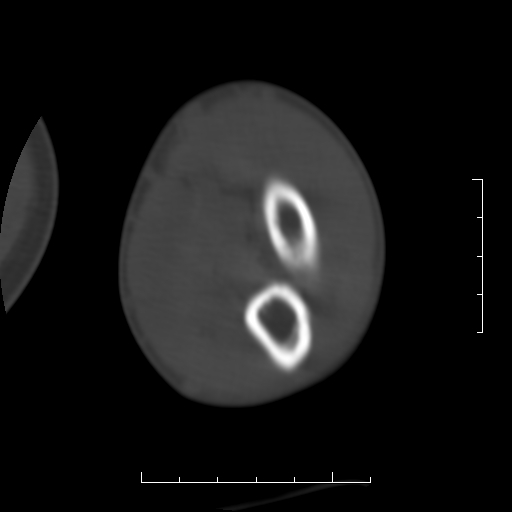

标题: CT8866:男27岁,正常吗?

患者男27岁,2007年3月查出患上肘关节滑膜结核,此后行手术滑膜剥除,今查ct

看一下上面的桡骨粗隆有问题吗?

桡骨粗隆有问题,术后改变

桡骨骨皮质破坏,结合病史考虑结核